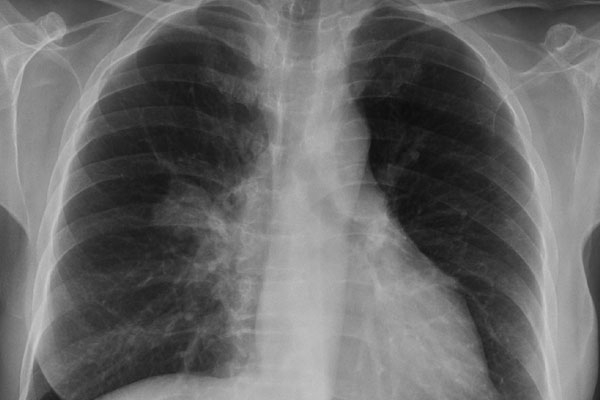

An anti-diabetic drug, metformin, may lower lung cancer risk in diabetic nonsmokers, as per the new study. The research at the Kaiser Permanente Division of Research in Oakland, California, suggested that metformin may prevent cancer, but the data from human studies is not supporting the report and said conflicting information.

Nonsmokers who used metformin for five years or longer had a 52 percent reduction in lung cancer risk, but this finding was not statistically acceptable. Five or more years of metformin usage was associated with a 31 percent decrease in the risk for adenocarcinoma of lung, the most common type of lung cancer diagnosed in nonsmokers, and an 82 percent increase in the risk for small-cell carcinoma, a type of lung cancer often diagnosed in smokers, but neither of these findings was statistically significant.